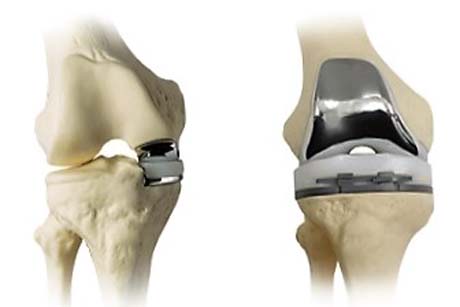

Τοποθέτηση του μηριαίου και του κνημιαίου εμφυτεύματος.

Άμεση σύγκριση της ολικής και της μονοδιαμερισματικής αρθροπλαστικής γόνατος.

Διατηρώντας τον πρόσθιο και τον οπίσθιο χιαστό σύνδεσμο καθώς και ανέπαφο το άλλο διαμέρισμα του ιδίου γόνατος και την επιγονατιδομηριαία άρθρωση, η μονοδιαμερισματική αρθροπλαστική θεωρείται ότι διατηρεί τη φυσιολογική κινηματική του γόνατος και επιτρέπει τη σχετικά εύκολη μετατροπή της σε ολική αρθροπλαστική σε απώτερο χρόνο.